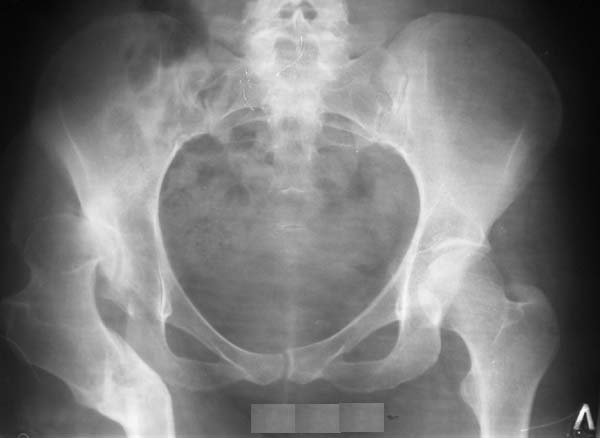

Уважаемые коллеги!Женщина, 35 летВ прошлом по поводу врожденного вывиха бедра перенесла операцию остеотомии по Шанцу

с удлинением правой ноги за счет бедра на уровне диафиза. В последнее время прогрессируют боли в правом тазобедренном суставе, порочное положение правой ноги, затруднена ходьба.Вопросы:1) Целесообразно ли эндопротезирование правого тазобедренного сустава?2) Целесообразный ли следующие действия: канал бедренной кости предполагаем вскрыть для введения ножки протеза на высоте угловой деформации, предполагаем низведение большого вертела с мышцами; протез будет подобран индивидуально, предполагается умеренная версия?В приложении рентгенограммы и трехмерная КТ.В цветном и более качественном варианте КТ размещена здесь